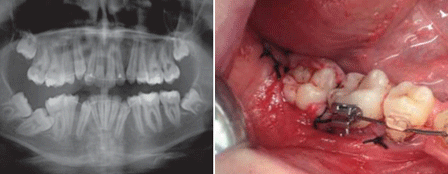

La decisión de exodonciar el segundo molar inferior viene determinado por varias circunstancias: 1. Posición del molar. Normalmente una posición muy horizontal hace que la única opción de tratamiento sea la extracción 2. El estado en el que se encuentre la pieza. Muchas veces la angulación mesiodistal provoca caries tanto en el primer molar por distal como en el mismo molar, estando la corona parcialmente destruida 3. Decisión del paciente de no hacer un tratamiento más largo y más costoso sin garantizar la viabilidad del tratamiento 4. Posibilidad de erupción del tercer molar en el lugar del segundo molar siempre que la posición del tercer molar sea favorable Reubicación quirúrgica del segundo molar impactado La opción de la correcta posición del segundo molar en el arco dentario según los artículos revisados es el tratamiento de elección en este tipo de casos. La reubicación y la colocación de aditamentos para logar su enderezamiento normalmente va seguido de la exodoncia del tercer molar en el mismo acto quirúgico. La reubicación del segundo molar inferior, se realiza haciendo una ostectomía liberadora a nivel distal y tras ella se procede a la elevación del molar de forma atraumática. El mejor momento para tratar los pacientes con un segundo molar impactado es la adolescencia (entre los 10 y 17 años), cuando las raíces del tercer molar no están formadas y las raíces del segundo molar, óptimamente, están formadas de un tercio a una mitad de su longitud total y sus ápices se mantienen abiertos. El arco de rotación en la reubicación no debe ser mayor de 90 grados, dado que si lo fuera, muy posiblemente estaríamos haciendo un autotrasplante y se disminuirían las posibilidades de una revascularización pulpar postquirúrgica (6). Normalmente se realiza una ostectomía liberadora alrededor del diente y una vez realizada la reubicación debe estabilizarse el diente y evitar los contactos oclusales. Debemos ser cuidadosos y no dañar, en la medida de lo posible, el cemento y el ligamento periodontal, así como reposicionar correctamente la encía queratinizada. No está indicada la utilización de materiales de relleno. Todo ello está relacionado con la consecución de una salud periodontal adecuada a largo plazo y una correcta regeneración ósea (6). Es deseable que el crecimiento vertical de la mandíbula esté próximo a ser completo, dado que se evitaría la posibilidad de que el diente reubicado quedara sumergido durante el crecimiento si no se diera una cicatrización periodontal adecuada. Respecto a la extracción del germen del tercer molar, existe consenso en que el tercer molar no puede considerarse como causa de la impactación del segundo molar inferior, dado que no interviene ni en el momento ni en la vía de erupción del segundo molar inferior. De hecho, su simple extracción no conlleva una erupción correcta de un segundo molar impactado. (13) Aunque algunos autores (15) apoyan su extracción cuando se realiza una exposición quirúrgica o una reubicación quirúrgica del segundo molar, pensamos que, si la intervención se realiza en pacientes con una edad óptima y el germen del tercer molar no dificulta la técnica quirúrgica, su extracción es una decisión exclusivamente ortodóncica, de forma que si el ortodoncista opina que habrá espacio para su erupción en el futuro su sacrificio no presenta ventaja alguna, a la vez que perdemos una opción terapéutica de futuro (el autotrasplante del germen del cordal) si el primer abordaje quirúrgico no tiene éxito.  Fig 1. 2º molar impactado Fig 2. Reubicación 2º molar  Fig 3 y 4. Ortopantomografia después del tratamiento.  Fig 5. Alambre trenzado para estabilizar al segundo molar. Exodoncia del segundo molar impactado y trasplante del tercer molar. Otra alternativa a la anterior, es la exodoncia del segundo molar inferior impactado y su inmediato trasplante en la posición idónea, o bien, trasplantar el tercer molar en el alveolo del segundo molar. Sin embargo, esta técnica presenta inconvenientes ya que el diente trasplantado tiene el riesgo de sufrir reabsorciones radiculares, patología pulpar y anquilosis, lo que disminuye el éxito del tratamiento Los resultados de las técnicas anteriores sugieren un mal pronóstico ya que la erupción del tercer molar en posición del segundo es casi siempre incompleta y existe el riesgo de extrusión de sus antagonistas superiores por el retraso en la erupción del tercer molar 12. Discusión En la mayoría de los estudios revisados, encontramos que la causa común de la impactación de los segundos molares es la falta de espacio en la arcada(2-6), sin embargo, se han descrito casos en los que la impactación ocurre cuando hay espacio suficiente para una erupción normal. La erupción del segundo molar es guiada por la raíz distal del primer molar ya erupcionado, y un exceso de espacio entre la corona en desarrollo y las raíces del primer molar producen la inclinación hacia mesial y la consecuente impactación del segundo molar11. En cuanto al tratamiento, los resultados encontrados en la literatura avalan que, por el grado de incidencia tan bajo y la gran diversidad clínica que presenta esta situación patológica, no existe un protocolo de tratamiento estándar para el seguimiento de estas retenciones.